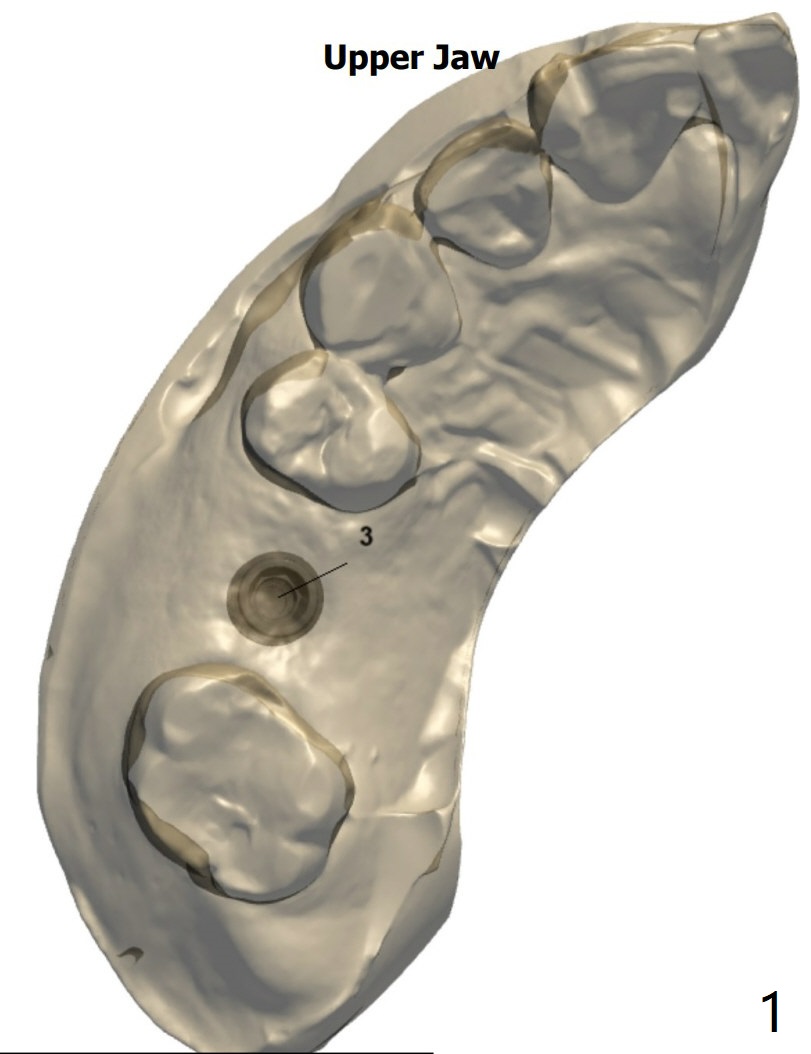

Wide Bone

A 52-year-old man requests implant at #3 and 31 a few months post socket preservation.